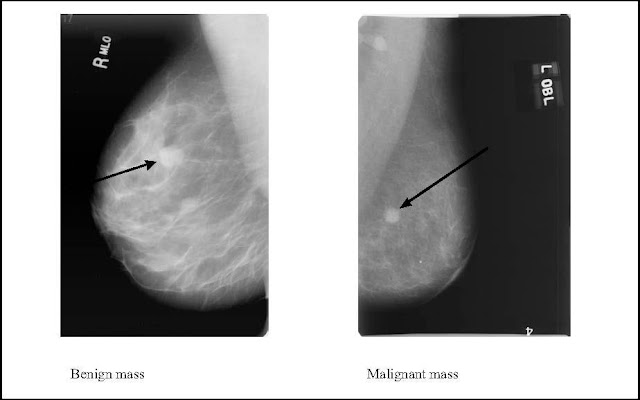

IMAGING DIAGNOSIS